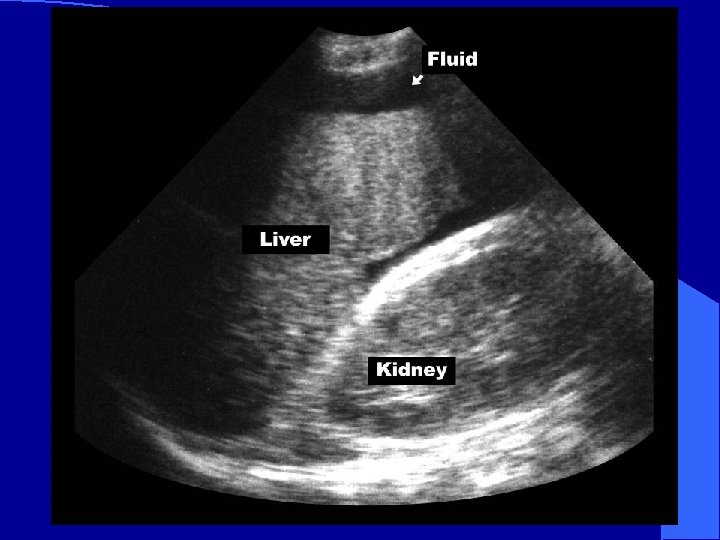

RUQ l Image on screen: – Liver cephalad – Kidney inferiorly – Morison’s Pouch*: space between Glisson’s capsule and Gerota’s fascia * *

Normal RUQ l Image kidney – Longitudinally – Transversely l Two toned structure – Cortex/medulla – Renal sinus

Appearance of blood l Fresh blood – Anechoic (black) l Coagulating blood – First hypoechoic – Later hyperechoic

Normal Morison’s Pouch Free fluid in Morison’s Pouch

To Evaluate the Thorax l Move probe – cephalad – longitudinal l Image Liver Diaphragm Pleural space

Hemothorax liver fluid diaphragm